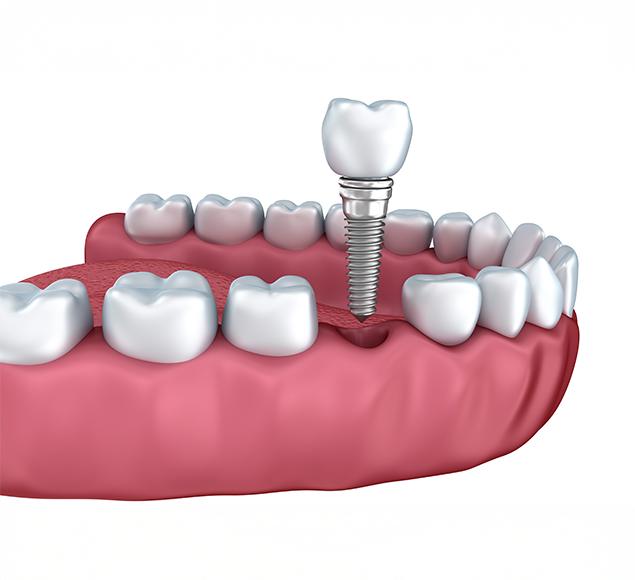

Dental implants are small titanium posts placed into the jawbone, where they act as replacement roots for missing teeth. Over time, the implant fuses naturally with the bone, a process called osseointegration, creating a stable foundation for a crown, bridge, or denture.

Beyond replacing missing teeth, implants can also help preserve the jawbone and prevent bone loss, which supports both oral health and overall facial structure.